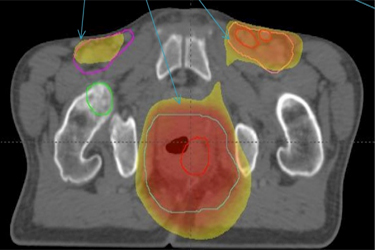

Πριν την θεραπεία ο ασθενής υποβάλλεται σε Αξονική Τομογραφία σχεδιασμού, όπου τοποθετείται σε συγκεκριμένη θέση θεραπείας. Μετά ακολουθεί σχεδιασμός της θεραπείας, προσδιορίζεται η περιοχή ακτινοβόλησης, ο όγκος στόχος και οι κρίσιμες δομές που πρέπει να προφυλαχτούν. Η θεραπεία γίνεται καθημερινά σε 28-30 συνεδρίες. Με την χορήγηση της IMRT τεχνικής μειώνεται η δερματική τοξικότητα, η αιματολογική τοξικότητα, οι παρενέργειες από το πεπτικό και το ουροποιητικό σύστημα.(εικ. 1,2)

ΚΑΡΚΙΝΟΣ ΤΟΥ ΠΡΩΚΤΟΥ IMRT –dose painting (προστασία των δομών)